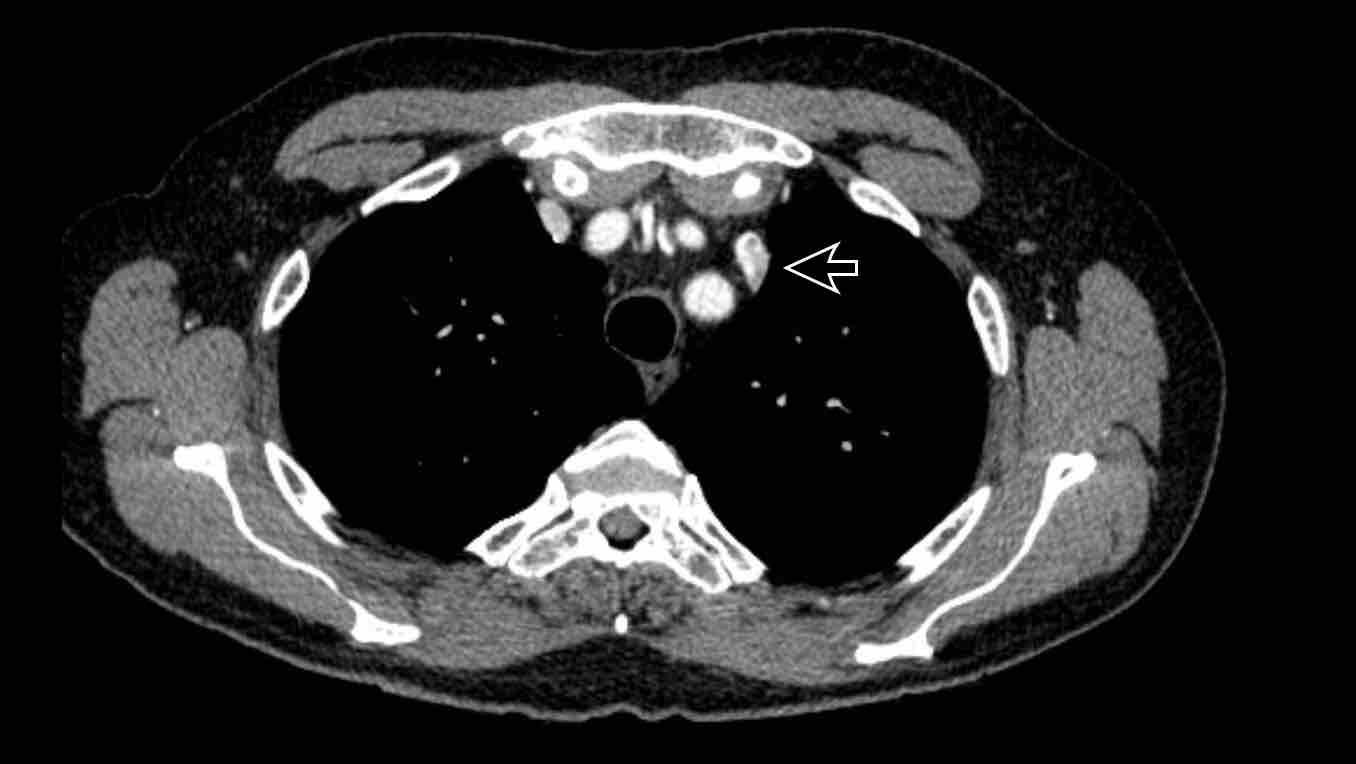

Hình ảnh

PAPVR bên trái phát hiện tình cờ với dẫn lưu trên tim của máu từ thùy trên trái vào tĩnh mạch tay đầu trái (các mũi tên).